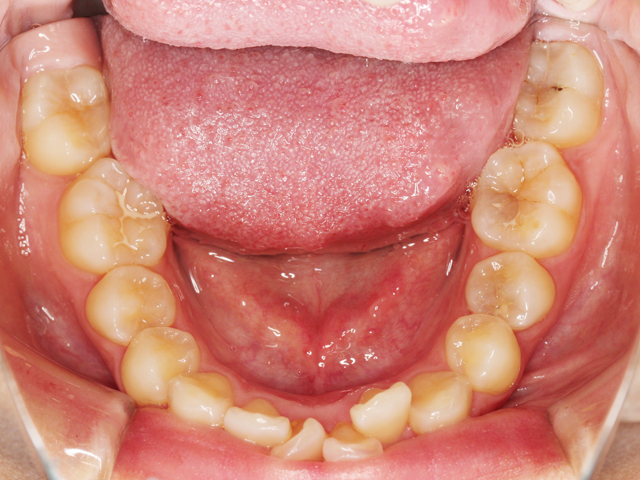

下顎の画像です。上と同じく前歯のスペースが不足しています。

右下の中切歯は「近心捻転(きんしんねんてん)」、左下の側切歯は「舌側転位」と呼ばれる状態になっています。